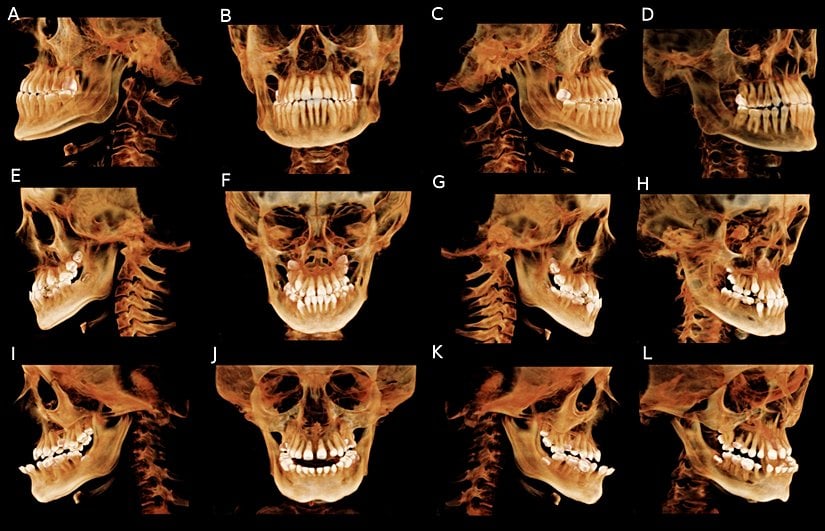

Hastalık sonucunda vücudun herhangi bir bölgesindeki ya da tümündeki kemiklerde gelişim bozuklukları ve kırılmalar meydana gelir. Örneğin kafatası kemiği, kol kemikleri, kaburgalar, bacak kemikleri, kalça kemikleri ve diğer kemiklerde sorunlar oluşur. Bu mutasyon vakaların %65'inde ebeveynlerden aktarılır, dolayısıyla gelişim sırasında kemikler vücut ağırlığı altında yeterli güçlü olamadıklarından eğilip bükülürler ve bu da vücut şekil bozukluklarına yol açar. Hastaların %35 civarında ise mutasyon "sporadik" olarak meydana gelir; yani bireyin kendi ömrü içerisinde oluşur.

Hastalık, genellikle X-ışını taraması gibi tıbbi görüntüleme teknikleri ve dışarıdan gözle görülebilir semptomlar ile teşhis edilir. Görüntüleme tekniklerinin kullanılma nedeni, vücut ekstremitleri ve omurgadaki bozulmaları teşhis etmektir. Belirtilerin Cam Kemik Hastalığı'ndan kaynaklandığı DNA analizi veya kolajen testiyle doğrulanabilir.